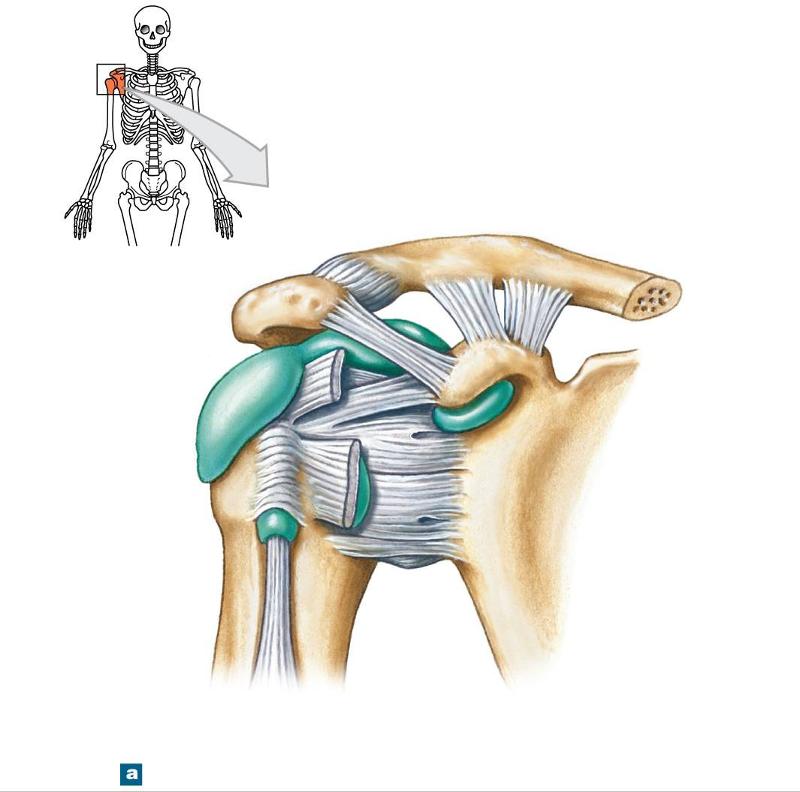

Glenohumeral ligament: анатомия и функции плечевого сустава